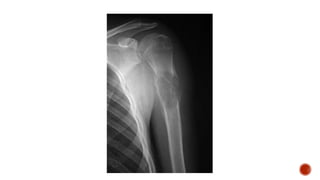

 Por lo general, la enfermedad se desarrolla en los huesos largos como el húmero, el

fémur, la tibia y la pelvis.

 Afecta a adolescentes y a adultos jóvenes Radiográficamente se observan imágenes

de áreas radiolúcidas con radiopacas, lo cual se denomina imágenes en "rayos de

sol", lo que indica que hay una neoformación de hueso.

 Histológicamente hay un predominio de osteocitos atípicos con formación de tejido

osteoide.

Osteosarcoma osteogénico  Porlo general, la enfermedad se desarrolla en los huesos largos como el húmero, el fémur, la tibia y la pelvis.  Afecta a adolescentes y a adultos jóvenes Radiográficamente se observan imágenes de áreas radiolúcidas con radiopacas, lo cual se denomina imágenes en "rayos de sol", lo que indica que hay una neoformación de hueso.  Histológicamente hay un predominio de osteocitos atípicos con formación de tejido osteoide.